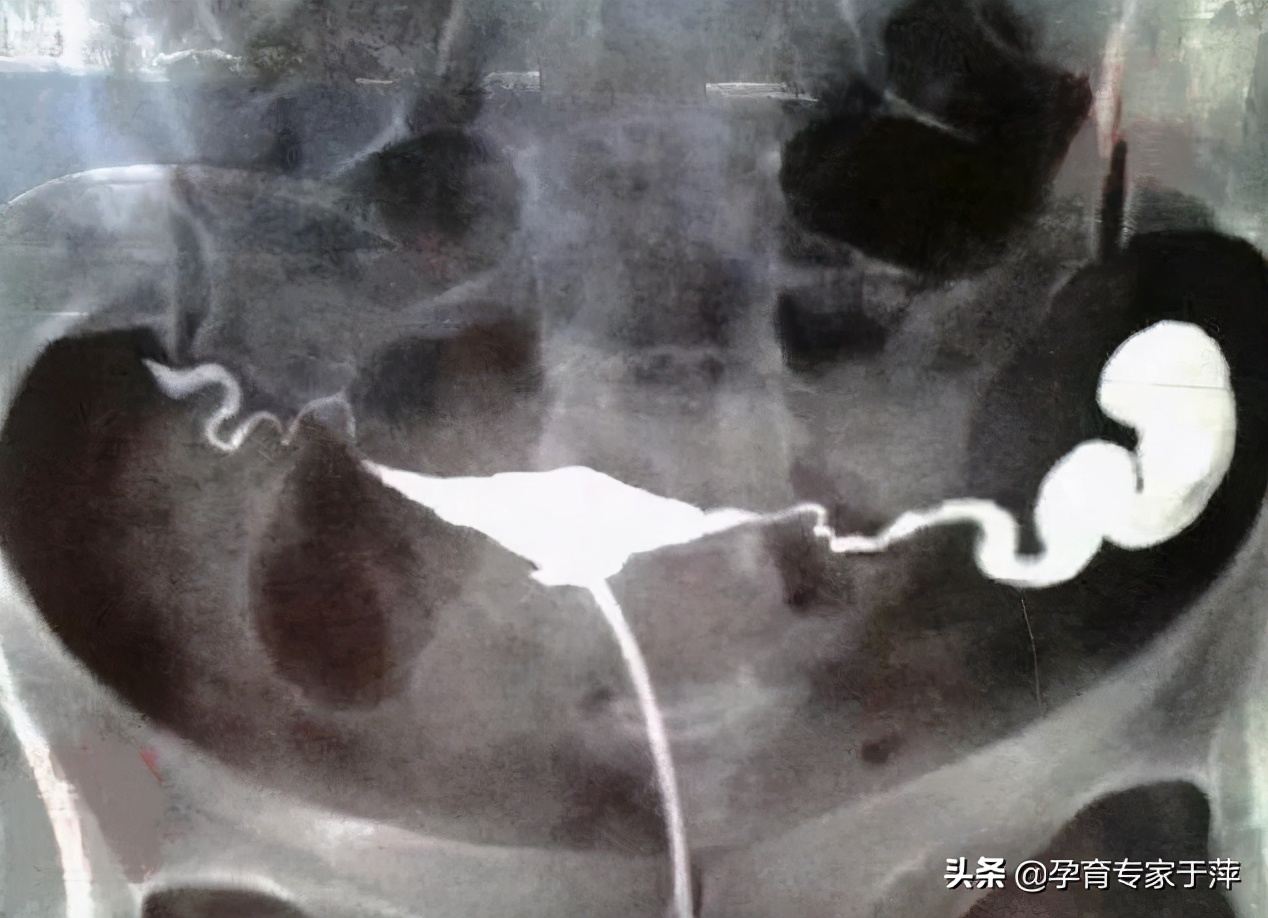

问:子宫输卵管造影提示“输卵管粘连”,我想自然受孕,可以手术治疗输卵管吗?

答:“输卵管粘连”是通过影像学检查对输卵管通畅程度的描述。粘连的表现及程度也各有不同。对于输卵管粘连造成的不孕可以首先考虑中医口服、灌肠、外敷三联法保守治疗,如保守治疗无效,再可以考虑手术。